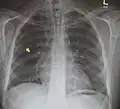

Pneumomediastinum is uncommon and occurs when air leaks into the mediastinum. The diagnosis can be confirmed via chest X-ray showing a radiolucent outline around the heart and mediastinum or via CT scanning of the thorax.

Pneumomediastinum with angel wing sign[15] -